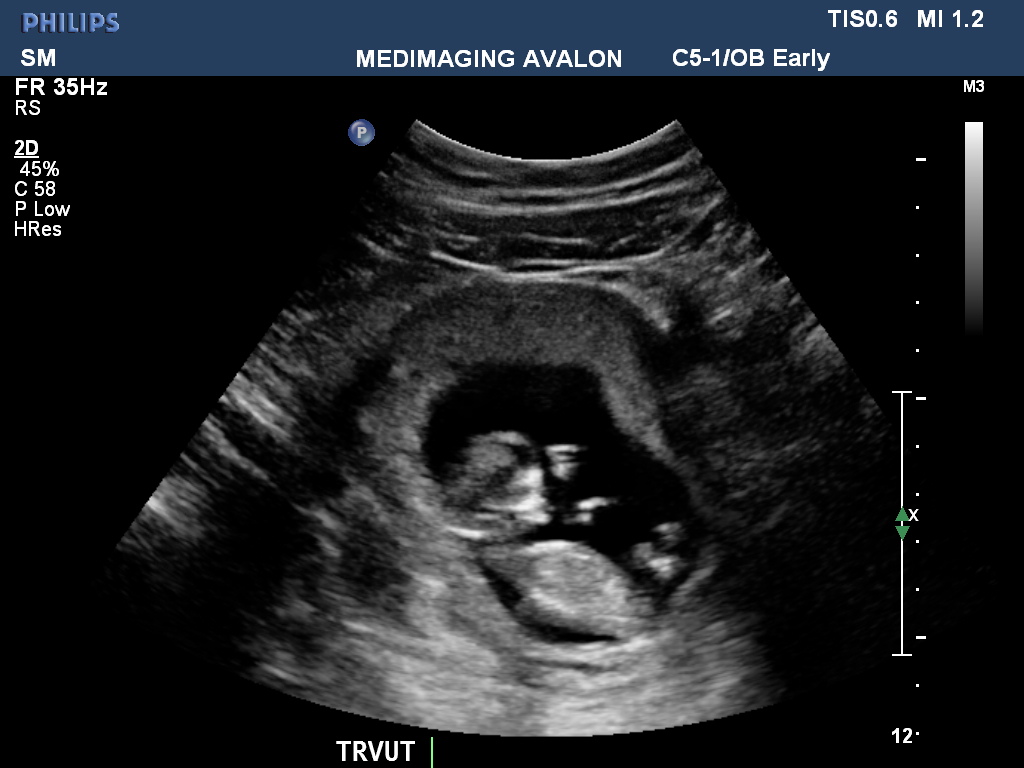

Today I had my nuchal screening ultrasound. All looks great! 11 weeks 4 days. Took all my power to not burst into tears seeing my little baby moving around like crazy. To all the mums out there waiting for their first ultrasound, it is so worth it! First time mum so its super awesome seeing this little miracle having a disco dance inside me! Just wanted to share my awesome news with all you awesome ladies

Have attached photo (u/s technician gave me a disc with lots of photos so tried to choose the best one)